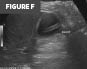

Figures F and G. Color Doppler and grayscale sonographic images. Images confirm the intraluminal position of the VP shunt catheter within the gallbladder, without wall thickening, pericholecystic fluid, or increased vascularity.

Given the presence of motion-related artifact on the initial CT, a gallbladder ultrasound was performed, confirming the intraluminal position of the VP shunt catheter (Figures F and G). Ultrasound further demonstrated the absence of gallbladder wall thickening or pericholecystic fluid—findings that would be expected in the setting of inadvertent catheter migration or erosion into the gallbladder.